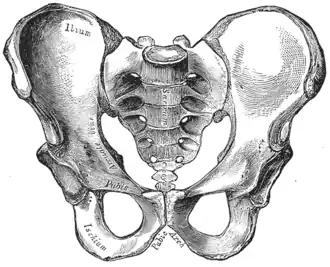

Female pelvis